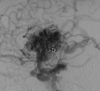

DX?

Infarto cerebral debido a ACM izq